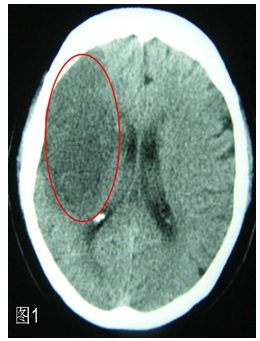

在某些地方也把头颅CT更形象地称作“脑扫描”。CT可以在最快的时间内了解,因为脑动脉堵塞而发生了脑梗死还是脑动脉破裂而出现了脑出血。脑梗死时头颅CT发现在脑组织出现了片状的黑色图像(图1),脑出血时可见在脑组织中出现了白色的团块(图2),一目了然。所以,得了脑卒中,第一要做的检查就是头颅CT。